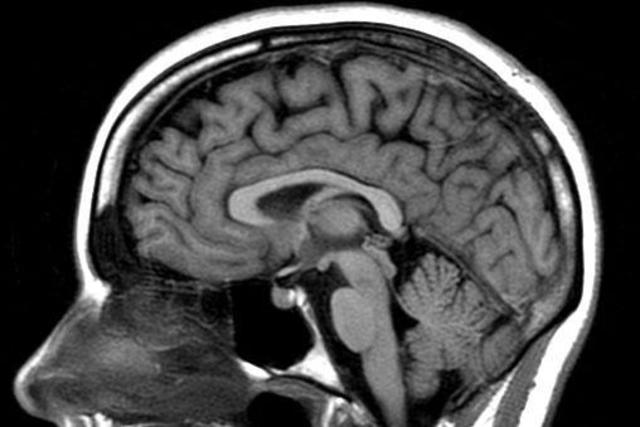

Son de un pez sin mandíbulas (los primeros vertebrados) con un patrón en su construcción que va a seguir como modelo a lo largo de toda la evolución, desde los vertebrados inferiores (peces, anfibios, y reptiles), siguiendo por los vertebrados superiores (aves y mamíferos), hasta llegar al hombre. Este tuvo una vida muy difícil durante el Paleolítico. Este modelo esta constituido por la médula espinal seguida del tronco del encéfalo, diencéfalo y eventualmente la corteza cerebral.

En los homínidos se considera que el comienzo del crecimiento del cerebro comenzó hace unos cinco o seis millones de años en el contexto específico de un determinado medio ambiente. Este nicho ecológico fue el encuentro o límite entre la selva húmeda, y la sabana árida y seca. En este medio ambiente cambiante sobrevinieron los primeros cambios adaptativos del cerebro en los antepasados del hombre. De ser ello así, pudo ser la temperatura ambiental en esta sabana, junto con métodos de caza.

A lo largo de la evolución de los mamíferos, desde hace mas de 60 millones de años, el desarrollo del cerebro se considera una primera y verdadera revolución en comparación al proceso conservador que había mantenido este desarrollo hasta entonces. Según Jerison (1973): “Con esta revolución nace la verdadera inteligencia es decir, la capacidad flexible de adoptar por diferentes opciones de respuesta ante un determinado estimulo. Esta revolución se expresa en los primeros mamíferos con una

Desde que se descubrió la verdadera importancia del cerebro su estudio ha estado avanzando a pasos agigantados. ... El cerebro humano moderno es el resultado de la evolución, relativamente rápida y constante, desde los primeros homínidos hasta el Homo sapiens sapiens.